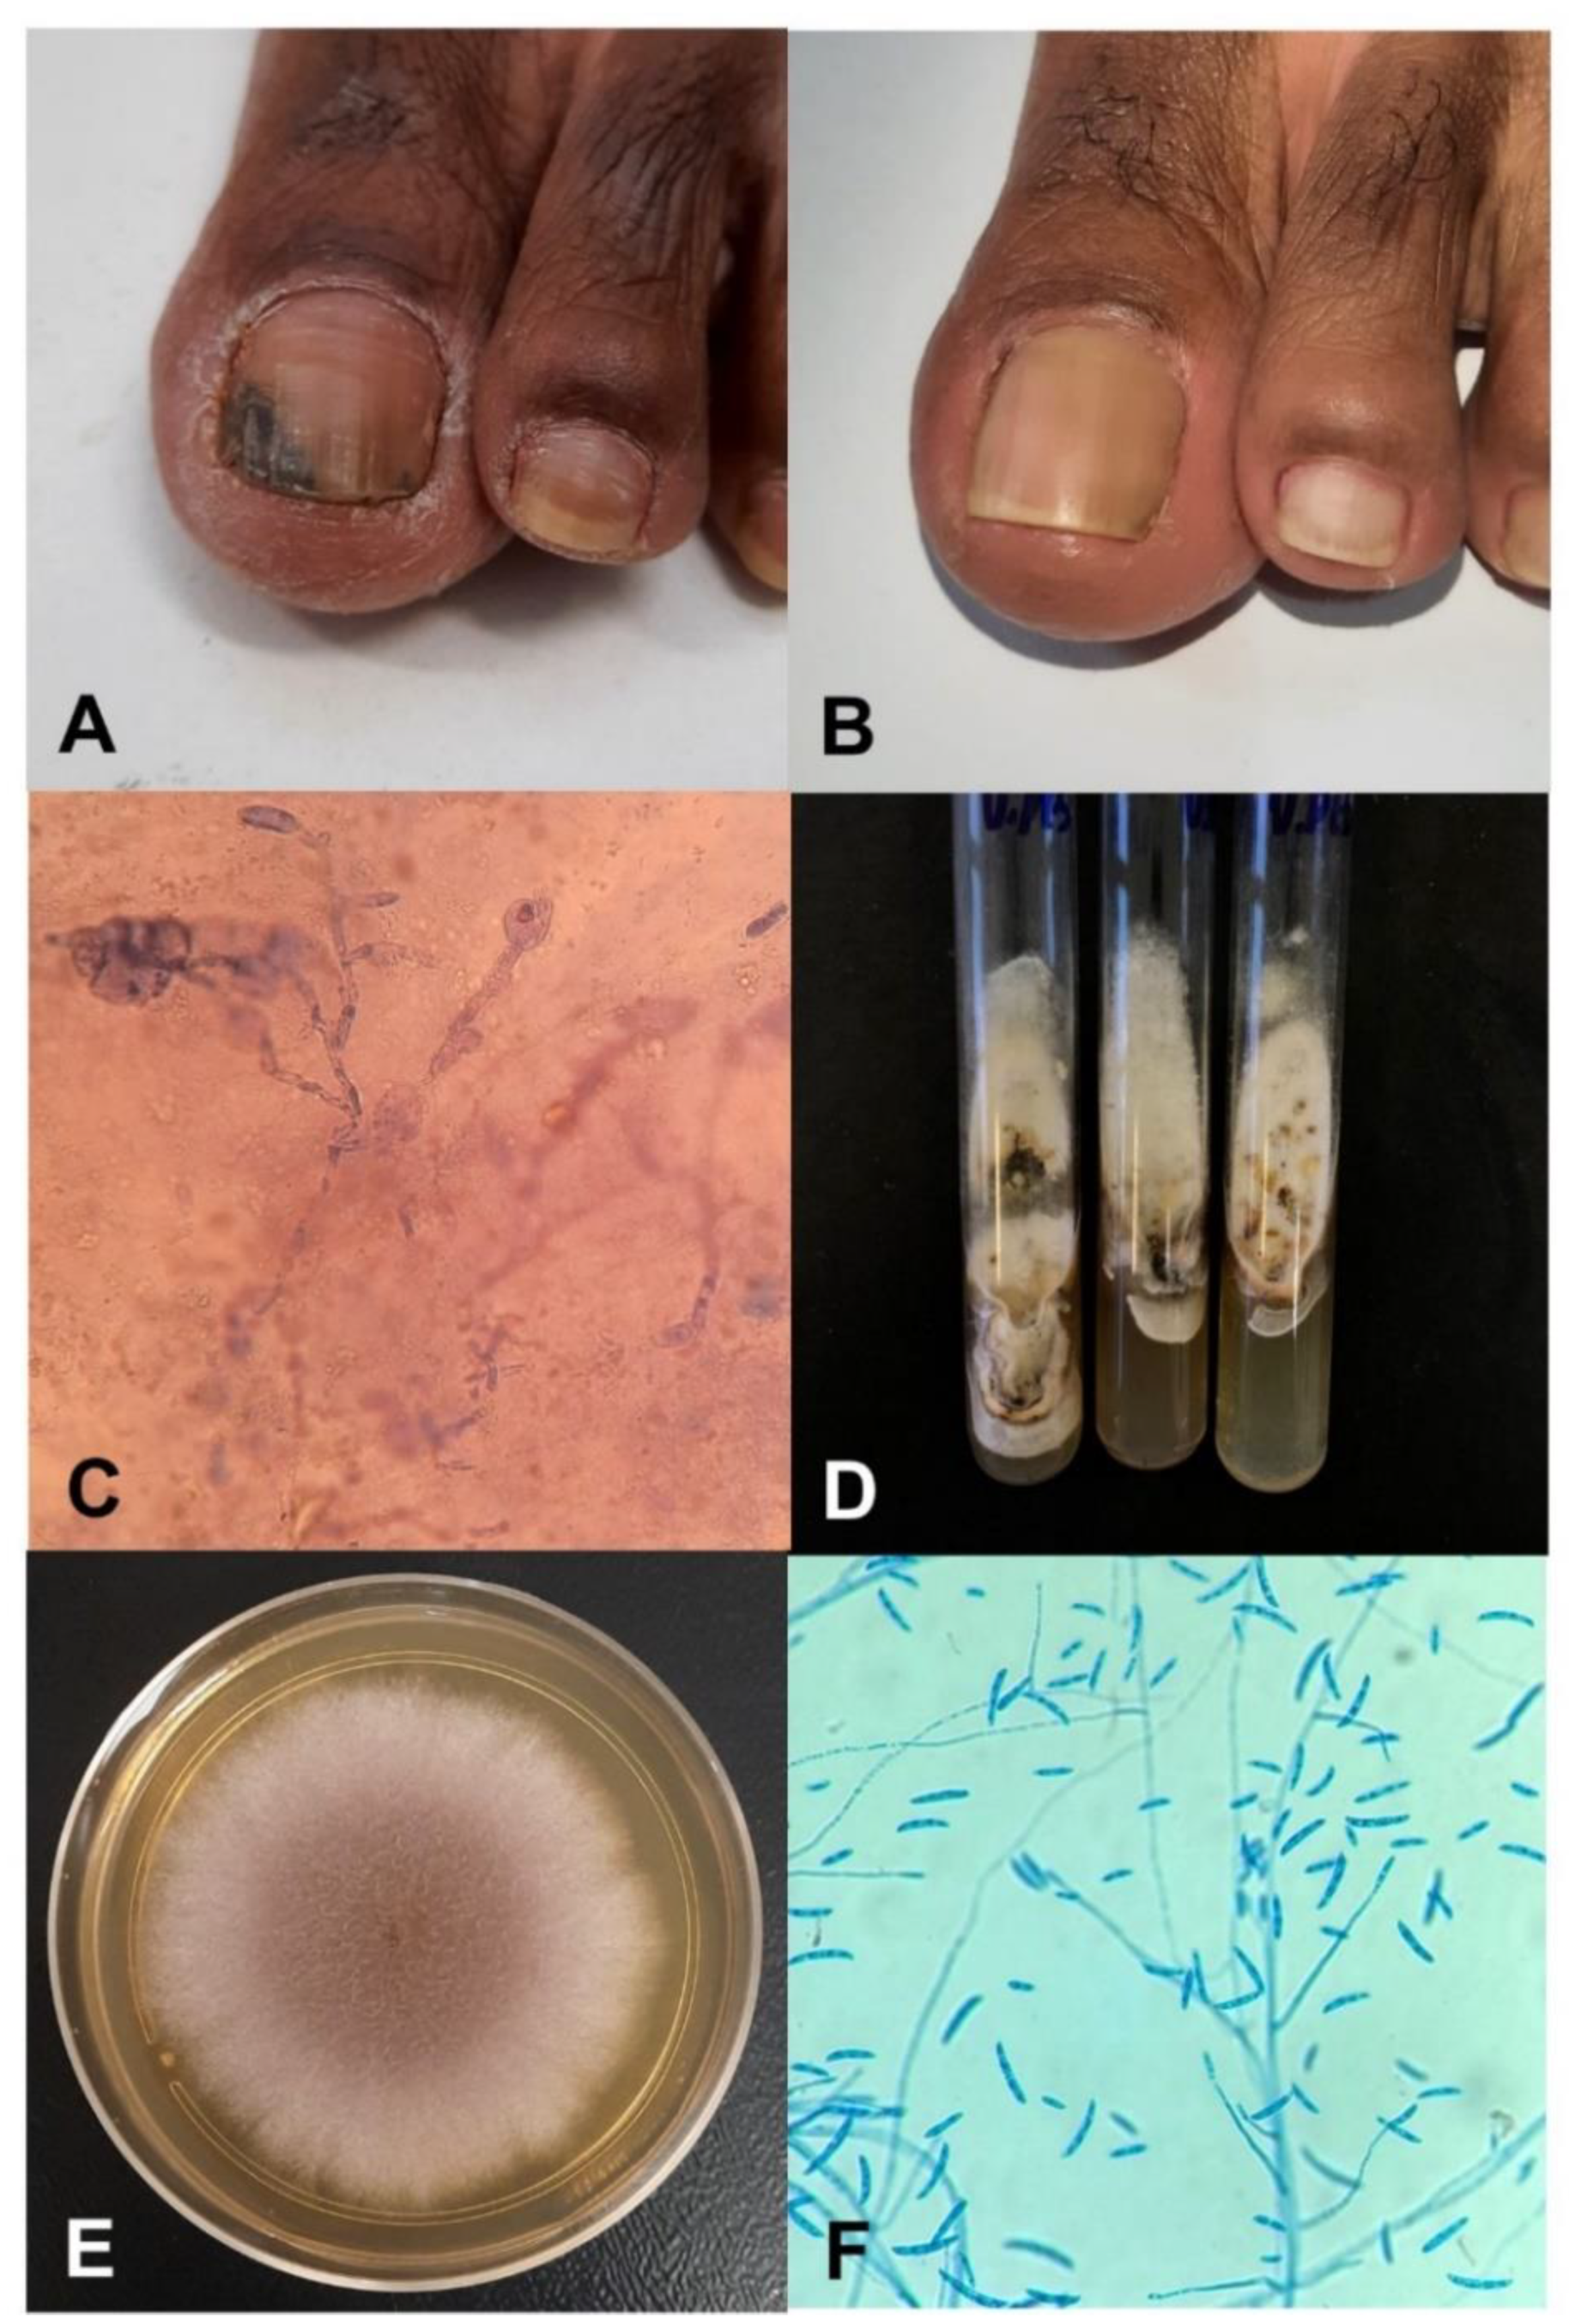

2.1. Fungus Origin and Patient’s History

2.2.3. Patient Treatment